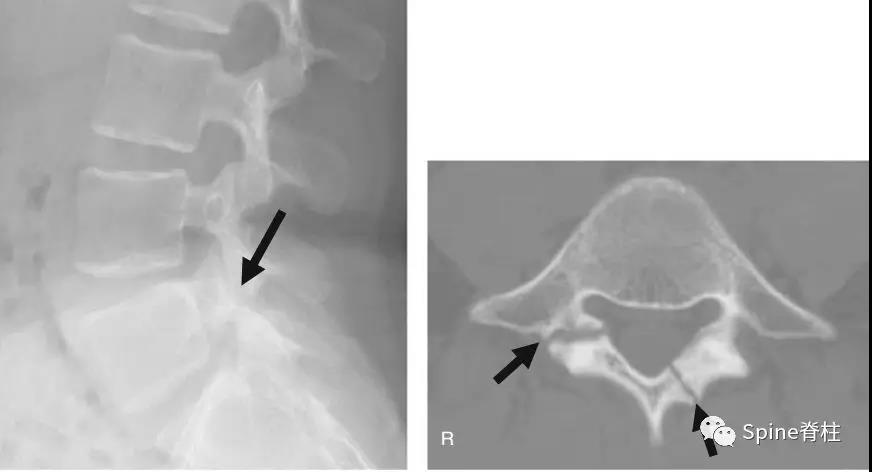

术中造影判断钉道是否合适

术中总会碰到吃不准钉道有没有穿透内壁的情况。确定方法有术中透视、电刀碰触试探、电生理监护、打开椎管直接探查等等。还有没有其他手段?——有的,用造影剂灌注钉道。